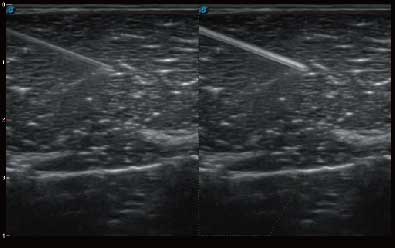

自动识别穿刺针进行声束智能偏转 手动修正多档调节 提高一次穿刺成功率